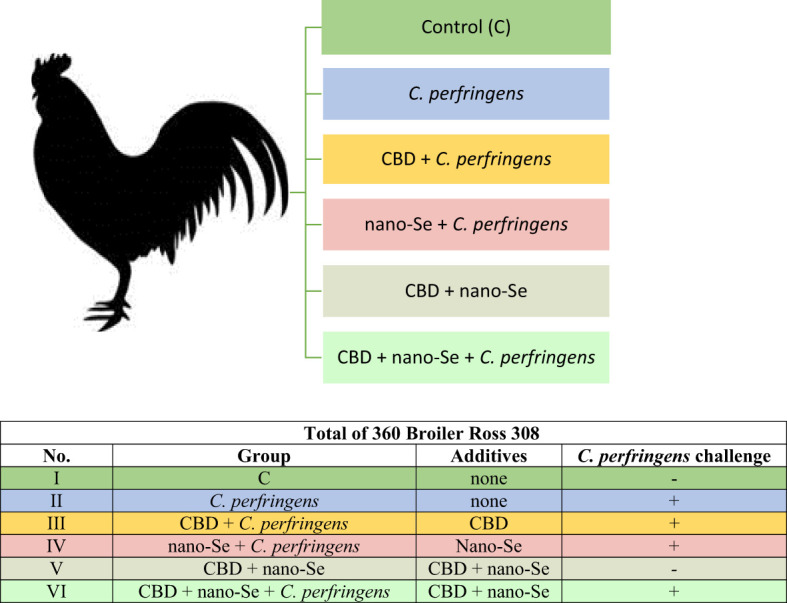

A total of 360 one-day-old male broiler chicks were purchased from a local hatchery. Upon arrival, the broilers were divided into six treatment groups with eight replicate cages of nine chickens per group according to average body weight. The conditions, such as temperature, light cycle and humidity, were maintained according to standard management practices for commercial chicken houses. Birds on days 0–8 were fed a starter diet, and a grower diet on days 9-23, which was formulated to meet or exceed the requirements for broiler chickens. The basal grower diet was based on wheat (50.76%), soybean meal (21.76%), triticale (15.54%), fish meal (5.18%), and rapeseed meal (4.15%) (ref. 32), which made the gut environment favorable for C. perfringens growth. Birds in the negative control (I, C) and positive control (II, C. perfringens) groups consumed a basal diet throughout the experiment. Groups CBD + C. perfringens (III) and nano-Se + C. perfringens (IV) were challenged and supplemented (on top) with 15 g/kg Cannabis sativa extract or with 0.3 mg/kg nano-Se. Chicks from CBD + nano-Se (V) group and CBD + nano-Se + C. perfringens (VI) were fed a control grower diet supplemented with both additives, but the second group was challenged with C. perfringens. The division into groups is shown in f1. A simple study design is shown in f2.